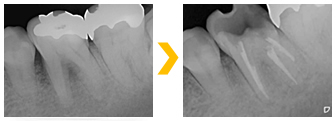

左下の奥歯に強い痛みを訴え来院。根管治療を施した。根管治療終了後、痛みはなくなり、炎症も認めないため、根管充填を施した。

左下の奥歯に強い痛みを訴え来院。根管治療を施した。根管治療終了後、痛みはなくなり、炎症も認めないため、根管充填を施した。